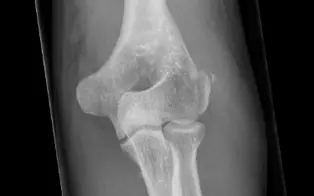

Fracture de la tete radiale